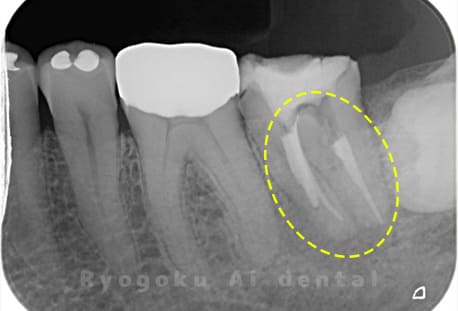

Case05

-

- 原因

- 慢性根尖性歯周炎

- 治療内容

- マイクロエンド

- 治療費用

- 121,000円(被せ物は含まない)

他院ではお薬の交換と抗生剤の処方で経過を診ていた患者さんです。歯茎の腫れが治らないとのことで、根管治療を開始し、2回目のご来院で腫れが引いたケースです。現在は被せ物も入り、良好に経過しております。

<リスク・副作用>

術後は痛み、腫れ、痺れなどの副作用が生じる場合があります。症状が再発する可能性があります。